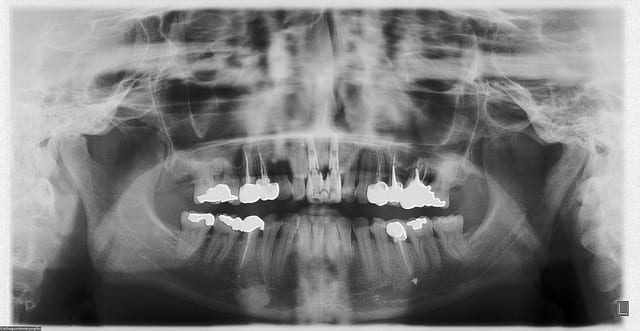

tien, ce matin, extraction de 24/25, curetage méticuleux, forage, comblement du gap, pose des 2 implants qui se sont bloqués à 50Ncm au CA sur les 3 ou 4 mm apicaux, pose des vis de cicat, sutures...35min....tranquille...

désolé, la pano est un poil déformée (la patiente à du bouger...)